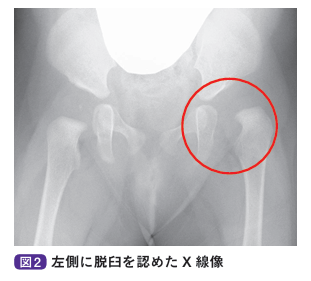

以前までは、奇形や麻痺などの合併がない乳幼児の股関節脱臼を認める状態を「先天性股関節脱臼」とよんできました。しかし、発症原因として母胎内での胎位以外に、出生時には股関節が完全脱臼していなくても寛骨臼形成不全(股関節の屋根となる寛骨臼の形成が悪い状態)のある症例や、出生後の抱き方、オムツの種類、おくるみの巻き方などにより脱臼してくるような後天性の症例があることから、最近では発育性股関節形成不全という呼称が一般的に用いられています。女児、家族歴、第1子、骨盤位分娩、冬生まれは発育性股関節形成不全のリスクが高くなるため、出生時より注意が必要です。

基本的に自覚症状はなく、股関節を90°以上に曲げてから外転した際に開排制限を認めます。股関節を開排したときに股関節が脱臼し、整復する際に指で音を感じた場合はクリックサイン陽性と判断します。一般的には、大腿皮膚溝は左右とも1-2本ですが、脱臼している場合は下肢の短縮により溝の数が増え、溝が深くなります。また、仰向けで両股関節・両膝関節を曲げて、両膝をそろえた際に膝の高さが異なることをアリスサイン陽性といいます。股関節脱臼があると大腿骨の長さが短くなるため、脱臼側の膝が低くなります。

基本的には単純X線像や超音波の検査を行います。そのほかに、必要に応じてMRIや股関節造影などを行う場合もあります。